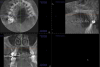

Other kinds of artifacts that are related to the CBCT technology itself may be present and compromise image quality, sometimes rather significantly.7 These artifacts are an inherent problem of CBCT and medical computed tomography because their appearance is a product of the reconstruction algorithms employed to compose the digital CBCT and CT images. In addition, the presence of any radiopaque materials is a frequent cause of artifacts. Metallic dental restorations, fixed prostheses, posts, and even gutta-percha may create artifacts that can obscure the visualization of the region of interest (Figure 3). As a result, fine diagnostic tasks may be impossible in proximity to restorations with high radiopacity. A number of CBCT manufacturers currently offer artifact reduction applications. These seem to have improved the resulting image quality; however, any possible gain in diagnostic efficiency has yet to be determined (Figure 4).

Beam hardening is another type of image artifact that is closely linked to the metallic artifact in CBCT images. These are dark, linear or cup-like bands near metallic restorations or implants, which may mimic osseous defects around dental implants or dental caries around restorations. Sometimes, their existence in combination with metallic artifacts in a heavily restored dentition may severely affect image quality to the degree that close anatomical structures like the crest of the alveolar ridge may be completely obscured. If fine detail is of the essence, in order to avoid metallic artifacts, it is sometimes advisable to remove any large restorations or posts from the teeth prior to scanning (if there was a plan to replace the restoration). Other times, increasing the slice thickness of the respective sections will reduce the deteriorating effects of the beam hardening and metallic artifacts.

(4.) When compared to the original CBCT image (left), the application of artifact reduc- tion algorithms have improved the visualization between the two dental implants (right image).

Figure 4